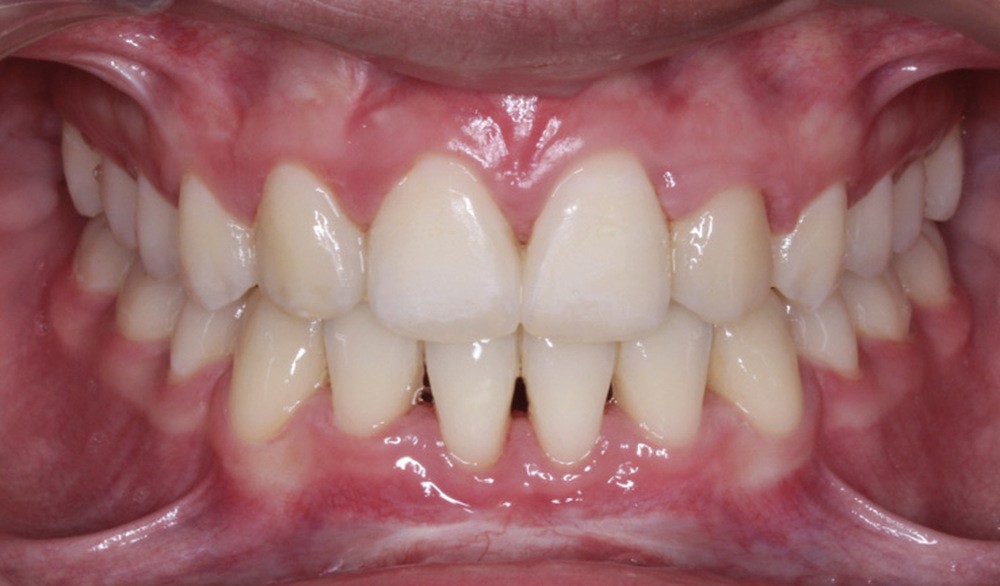

Les caches esthétiques ont été progressivement diminués jusqu’à leur suppression complète. Une fois l’alignement des canines obtenu, la prise en charge de 11 et 21 sur un NiTi .014 a débuté. Des forces très douces avec un contrôle radiologique tous les trois mois ont ensuite permis l’alignement et la fermeture des derniers espaces maxillaires. Une coronoplastie soustractive de 13 et 23 a été réalisée pour les transformer en 12 et 22. La vitalité de 11 et 21 a été conservée. En contention, deux fils collés ont été mis en place (13-23 et 33-43) ainsi qu’une gouttière thermoformée maxillaire amovible à port nocturne. Le traitement a duré vingt-neuf mois (fig. 5a-f).

Le traitement a permis d’améliorer l’environnement parodontal et de mettre en place les canines incluses tout en préservant au maximum les incisives centrales déjà résorbées et en assurant un résultat esthétique pour la patiente.